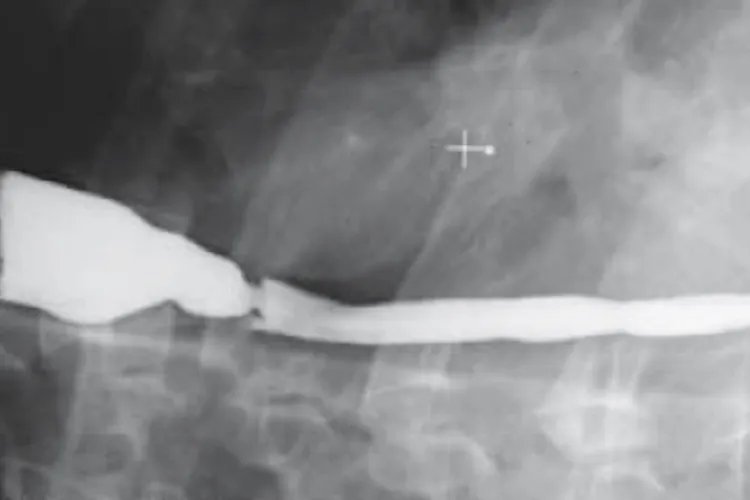

病因本病主要是由于食管下段括约肌压力低下,导致胃酸反流至食管,使食管暴露于胃酸时间过长而引起食管黏膜损害。主要与食管裂孔疝、妊娠、呕吐、呃逆、外科手术、以及各种器质性疾病,如食管下段及贲门部肿瘤、硬皮病和各种造成幽门梗阻的疾病有关。诊断本病可根据临床症状和内镜检查进行诊断。有明显的反流症状,可作出初步临床诊断,内镜下发现反流性食管炎表现即可诊断。此外,还可做X线钡餐造影、24小时食管pH监测、食管测压等检查,以判断反流情况和食管情况。治疗本病以非手术治疗为主,肥胖病人应减轻体重,避免持重、弯腰等动作,勿穿过紧衣裤。睡眠时抬高床头15cm,睡前6小时勿进食。药物治疗可应用制酸剂、促胃动力药物、抑酸剂、黏膜保护剂。因反流性食管炎形成的瘢痕性狭窄,对有吞咽困难症状者可行食管扩张术。此外,部分符合手术指征者可进行外科手术治疗。